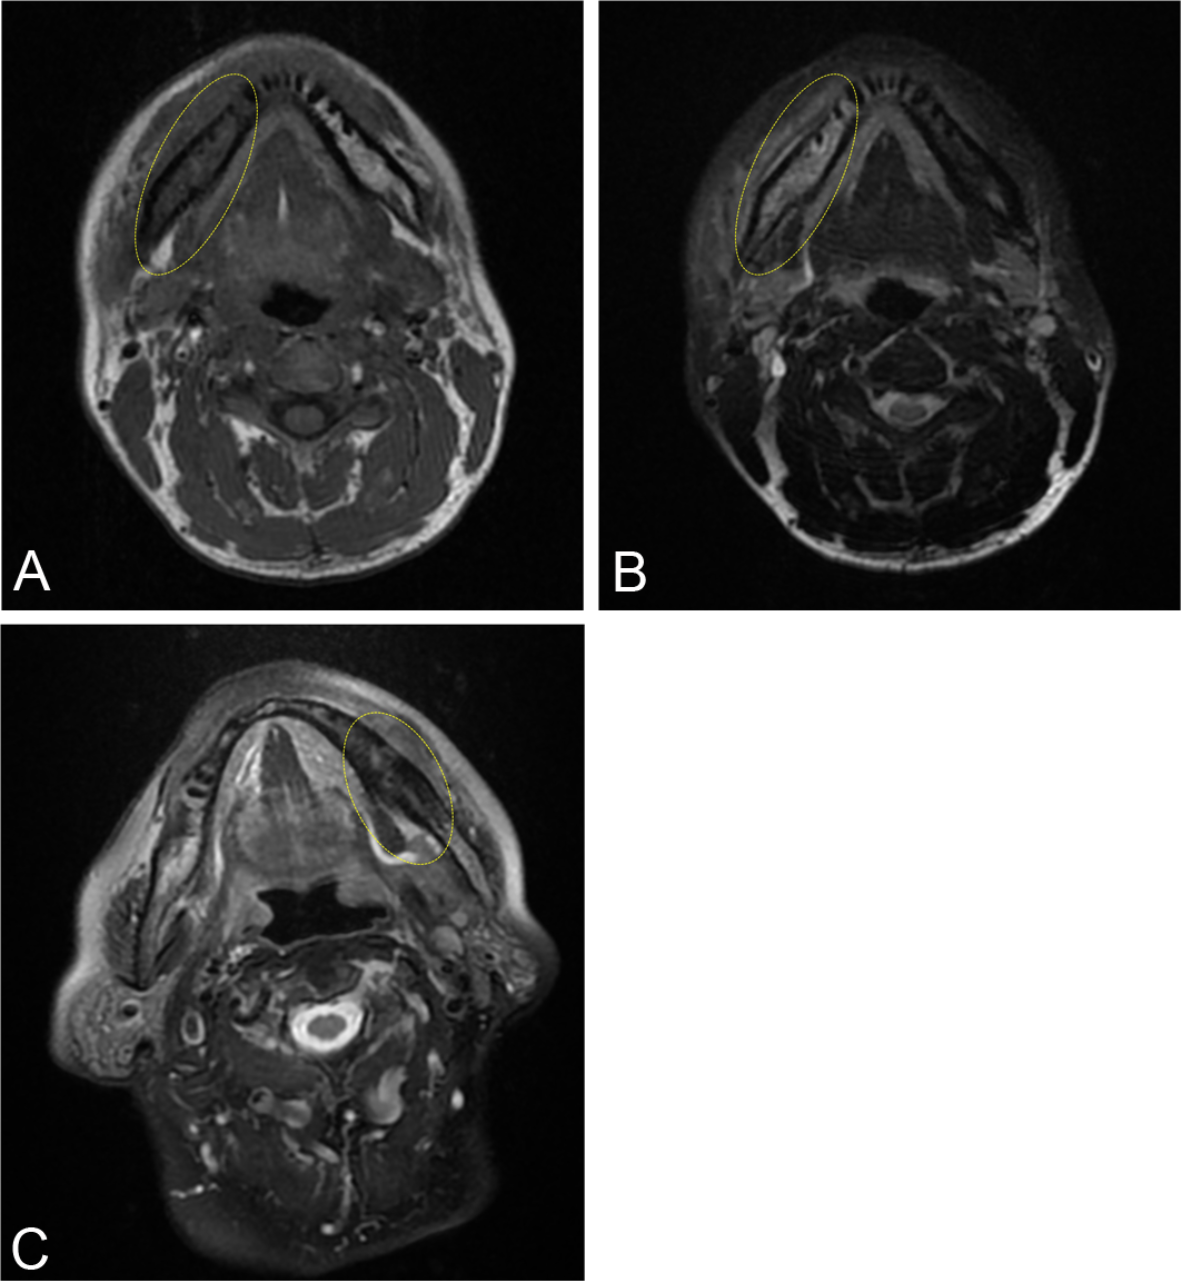

Fig. 8

Examples of MR signal intensities of lesions compared with those of the contralateral side. A 39-year-old male presented at a local clinic with pain and swelling on the right side of the mandible. Root canal treatment was performed on the right lower first molar, but the swelling did not improve. He also developed abnormal sensation of the mental nerve and was referred to our hospital. (A) T1-weighted image showing low signal intensity compared with the healthy side (ellipse). (B) T2-weighted fat-suppressed image showing high signal intensity compared with the healthy side (ellipse). An 86-year-old female presented at a local clinic with swelling in the left lower molar region of the mandible. She was treated with alendronate for osteoporosis and was referred to our clinic. (C) T2-weighted fat-suppressed image showing low signal intensity compared with the healthy side (ellipse).